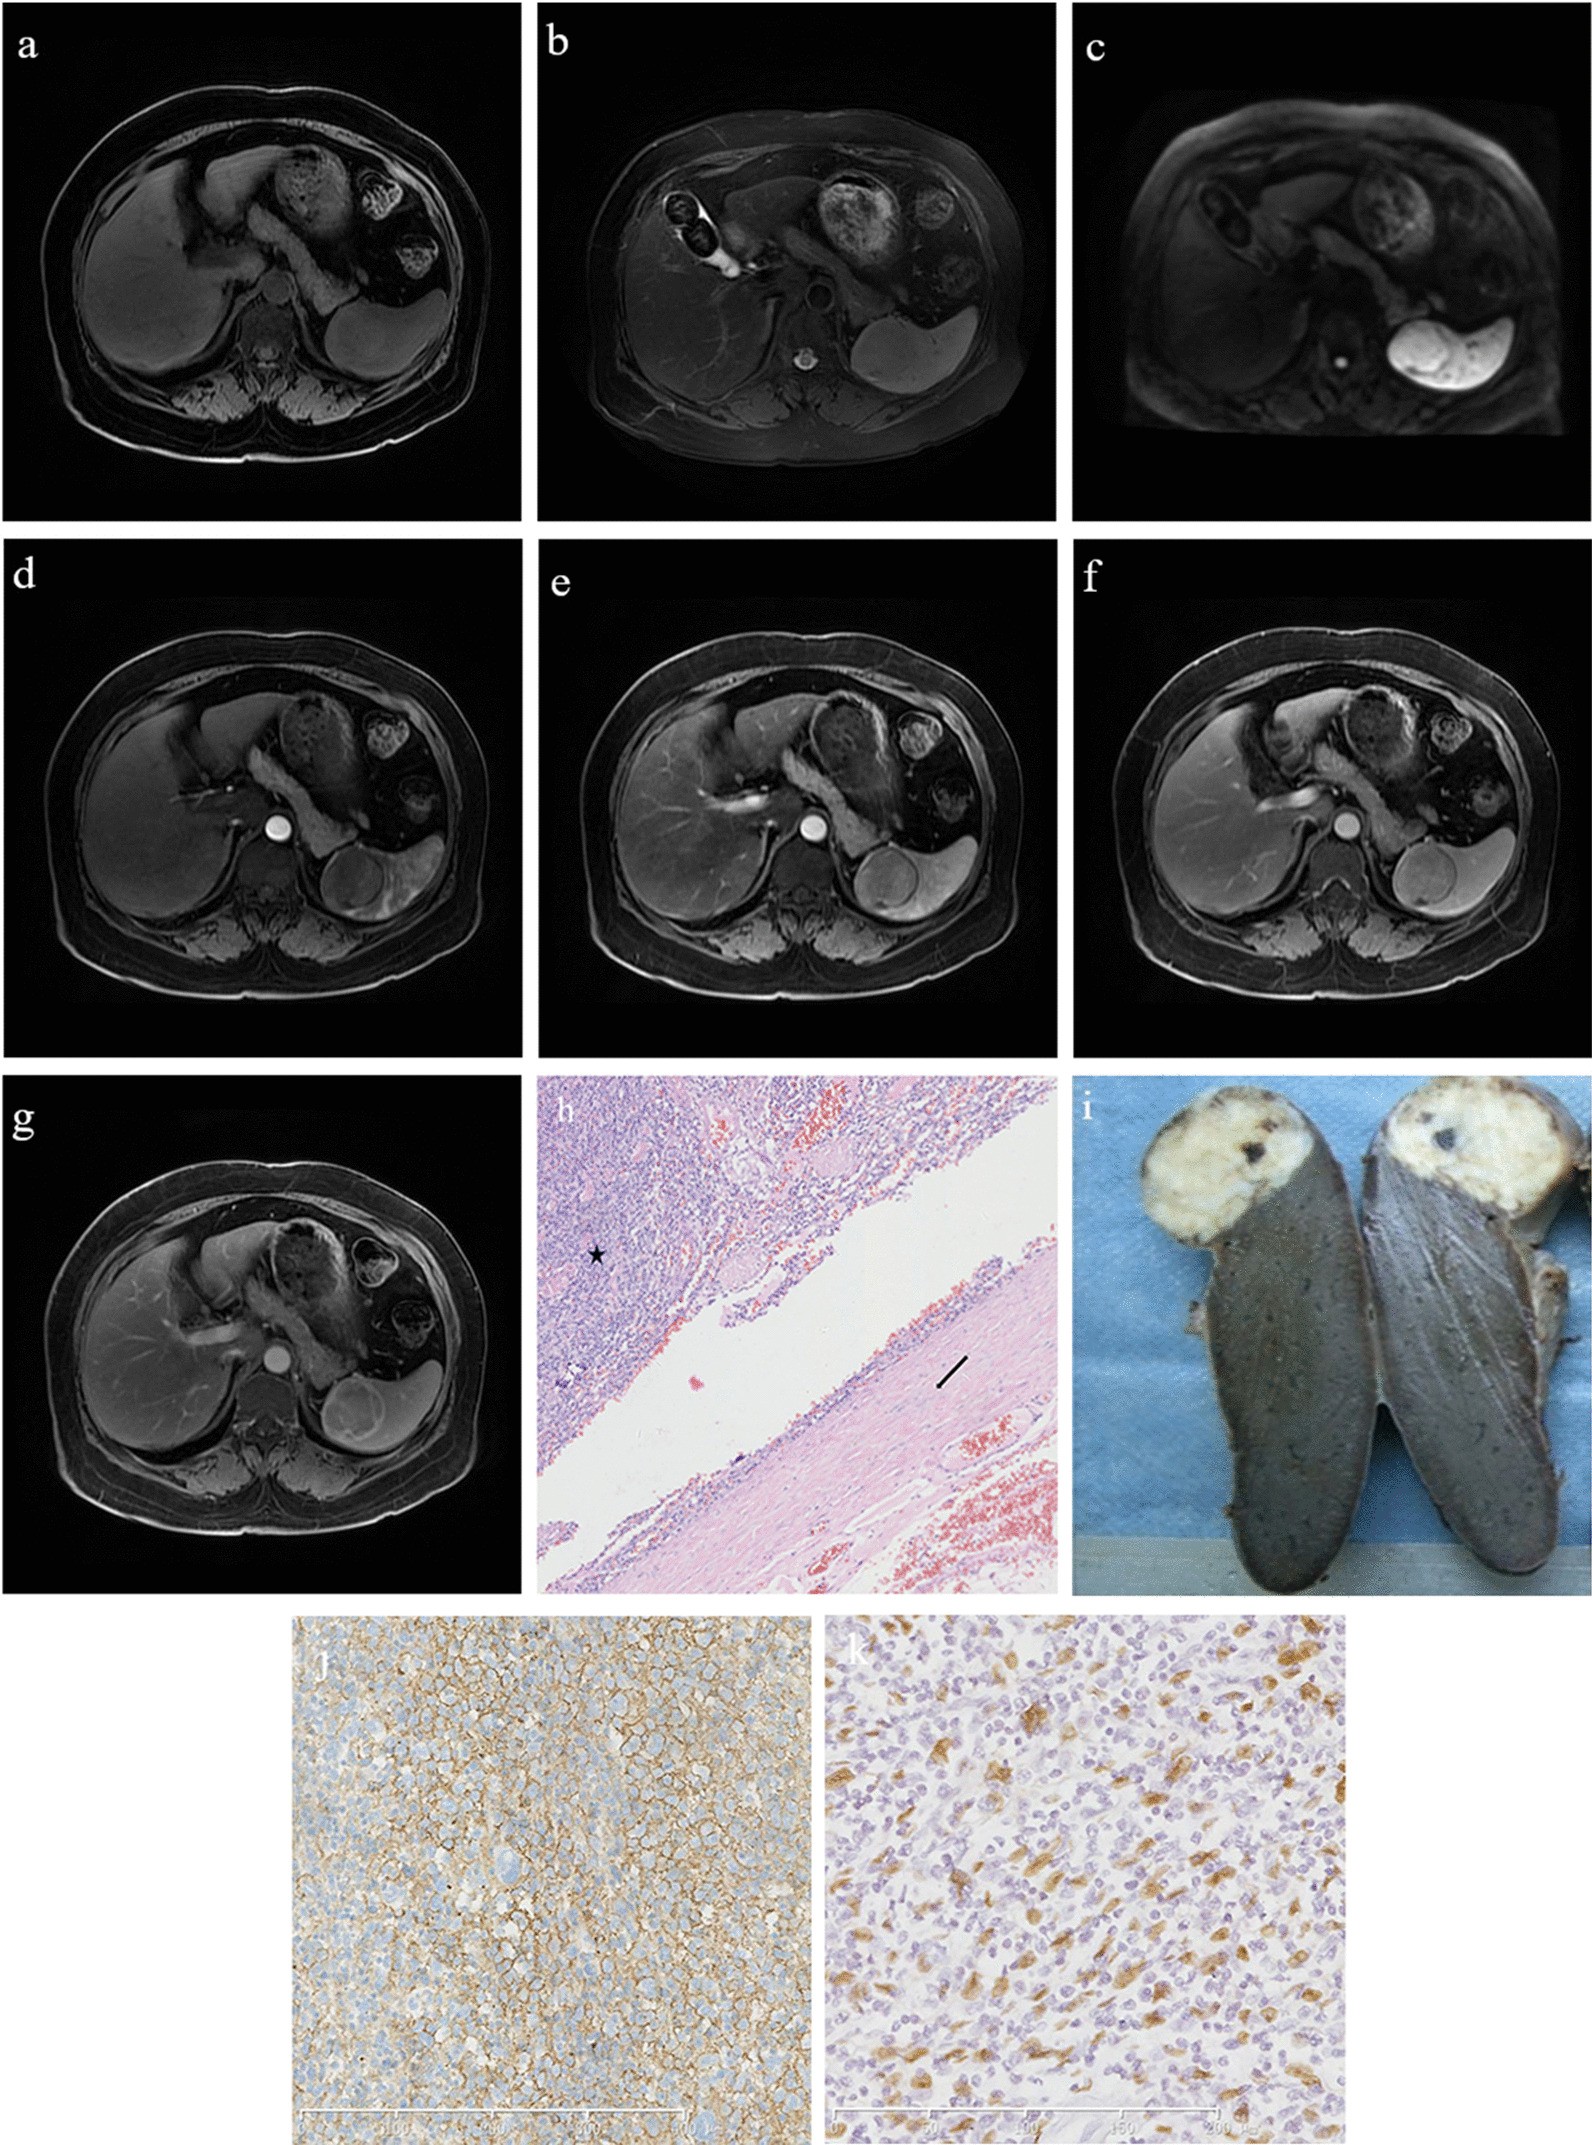

Fig. 5

A 37-year-old male patient with inflammatory pseudotumor-like follicular dendritic cell sarcoma of the spleen. a The mass shows a slight hyperintensity on the T1-weighted image sequence. b On the T2-weighted image sequence, the tumor shows a slightly hypointense signal, and its edge displays a hypointense annular signal representing the pseudocapsule. c The mass shows a slightly hyperintense signal on diffusion-weighted imaging. d–g The contrast enhancement of the mass is mild in each phase, and the pseudocapsule shows delayed enhancement. h On histopathological examination, the tumor (black star) is surrounded by dense fibrous tissue (black arrow; hematoxylin and eosin, ×100). i Macroscopic examination showing a grayish-white tumor with uniform texture and clear boundaries. j CD21 is diffusely positive. k Epstein–Barr virus is detected in almost all of the tumor cells with positive dark staining of their nuclei